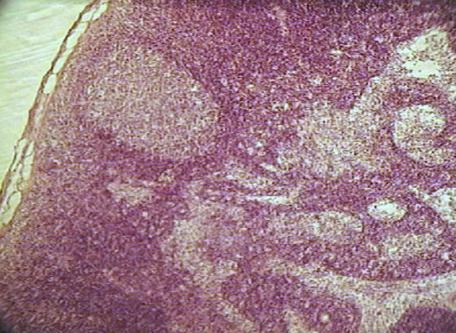

Фото. 2.3.1. Лимфатический узел. Гем.-Эоз.

Малое увеличение. (Ув.10х7)

Под соединительнотканной оксифильно окрашенной капсулой узла (плотная неоформленная соединительная ткань) расположены лимфатические фолликулы коркового вещества синего цвета. Большинство фолликулов имеют выраженный светлый центр и более темный венец из лимфоцитов. Центральную часть лимфатического узла занимает мозговое вещество, в котором различают окрашенные базофильно мозговые тяжи – структуры состоящие в основном, из плазматических клеток. Лимфоциты маскируют ретикулярную ткань, ее можно увидеть только в синусах узла при большом увеличении микроскопа. В синусах узла расположено значительное количество клеток: малых лимфоцитов, макрофагов.

б) найти корковое вещество узла. Состоит из базофильно окрашенных лимфатических фолликулов, расположенных по периферии. В корковом веществе узла на гистологическом препарате фолликулы часто расположены в несколько рядов, если срез проведен не по центру органа и, как правило, на таких препаратах плохо выражено мозговое вещество.

в) найти мозговое вещество узла. По сравнению с корковым веществом, мозговое более светлое. В нем располагаются мозговые тяжи (базофильно окрашенные) и мозговые синусы.

г) найти паракортикальную зону на границе коркового и мозгового вещества. Паракортикальная зона расположена непосредственно под лимфатическими фолликулами и не имеет четких границ.

д) найти краевой (подкапсулярный) синус - светлое пространство между капсулой и лимфатическими фолликулами, заполненное клетками.

е) найти вокругузелковый синус - светлое пространство между трабекулами и лимфатическими фолликулами, заполненное клетками.